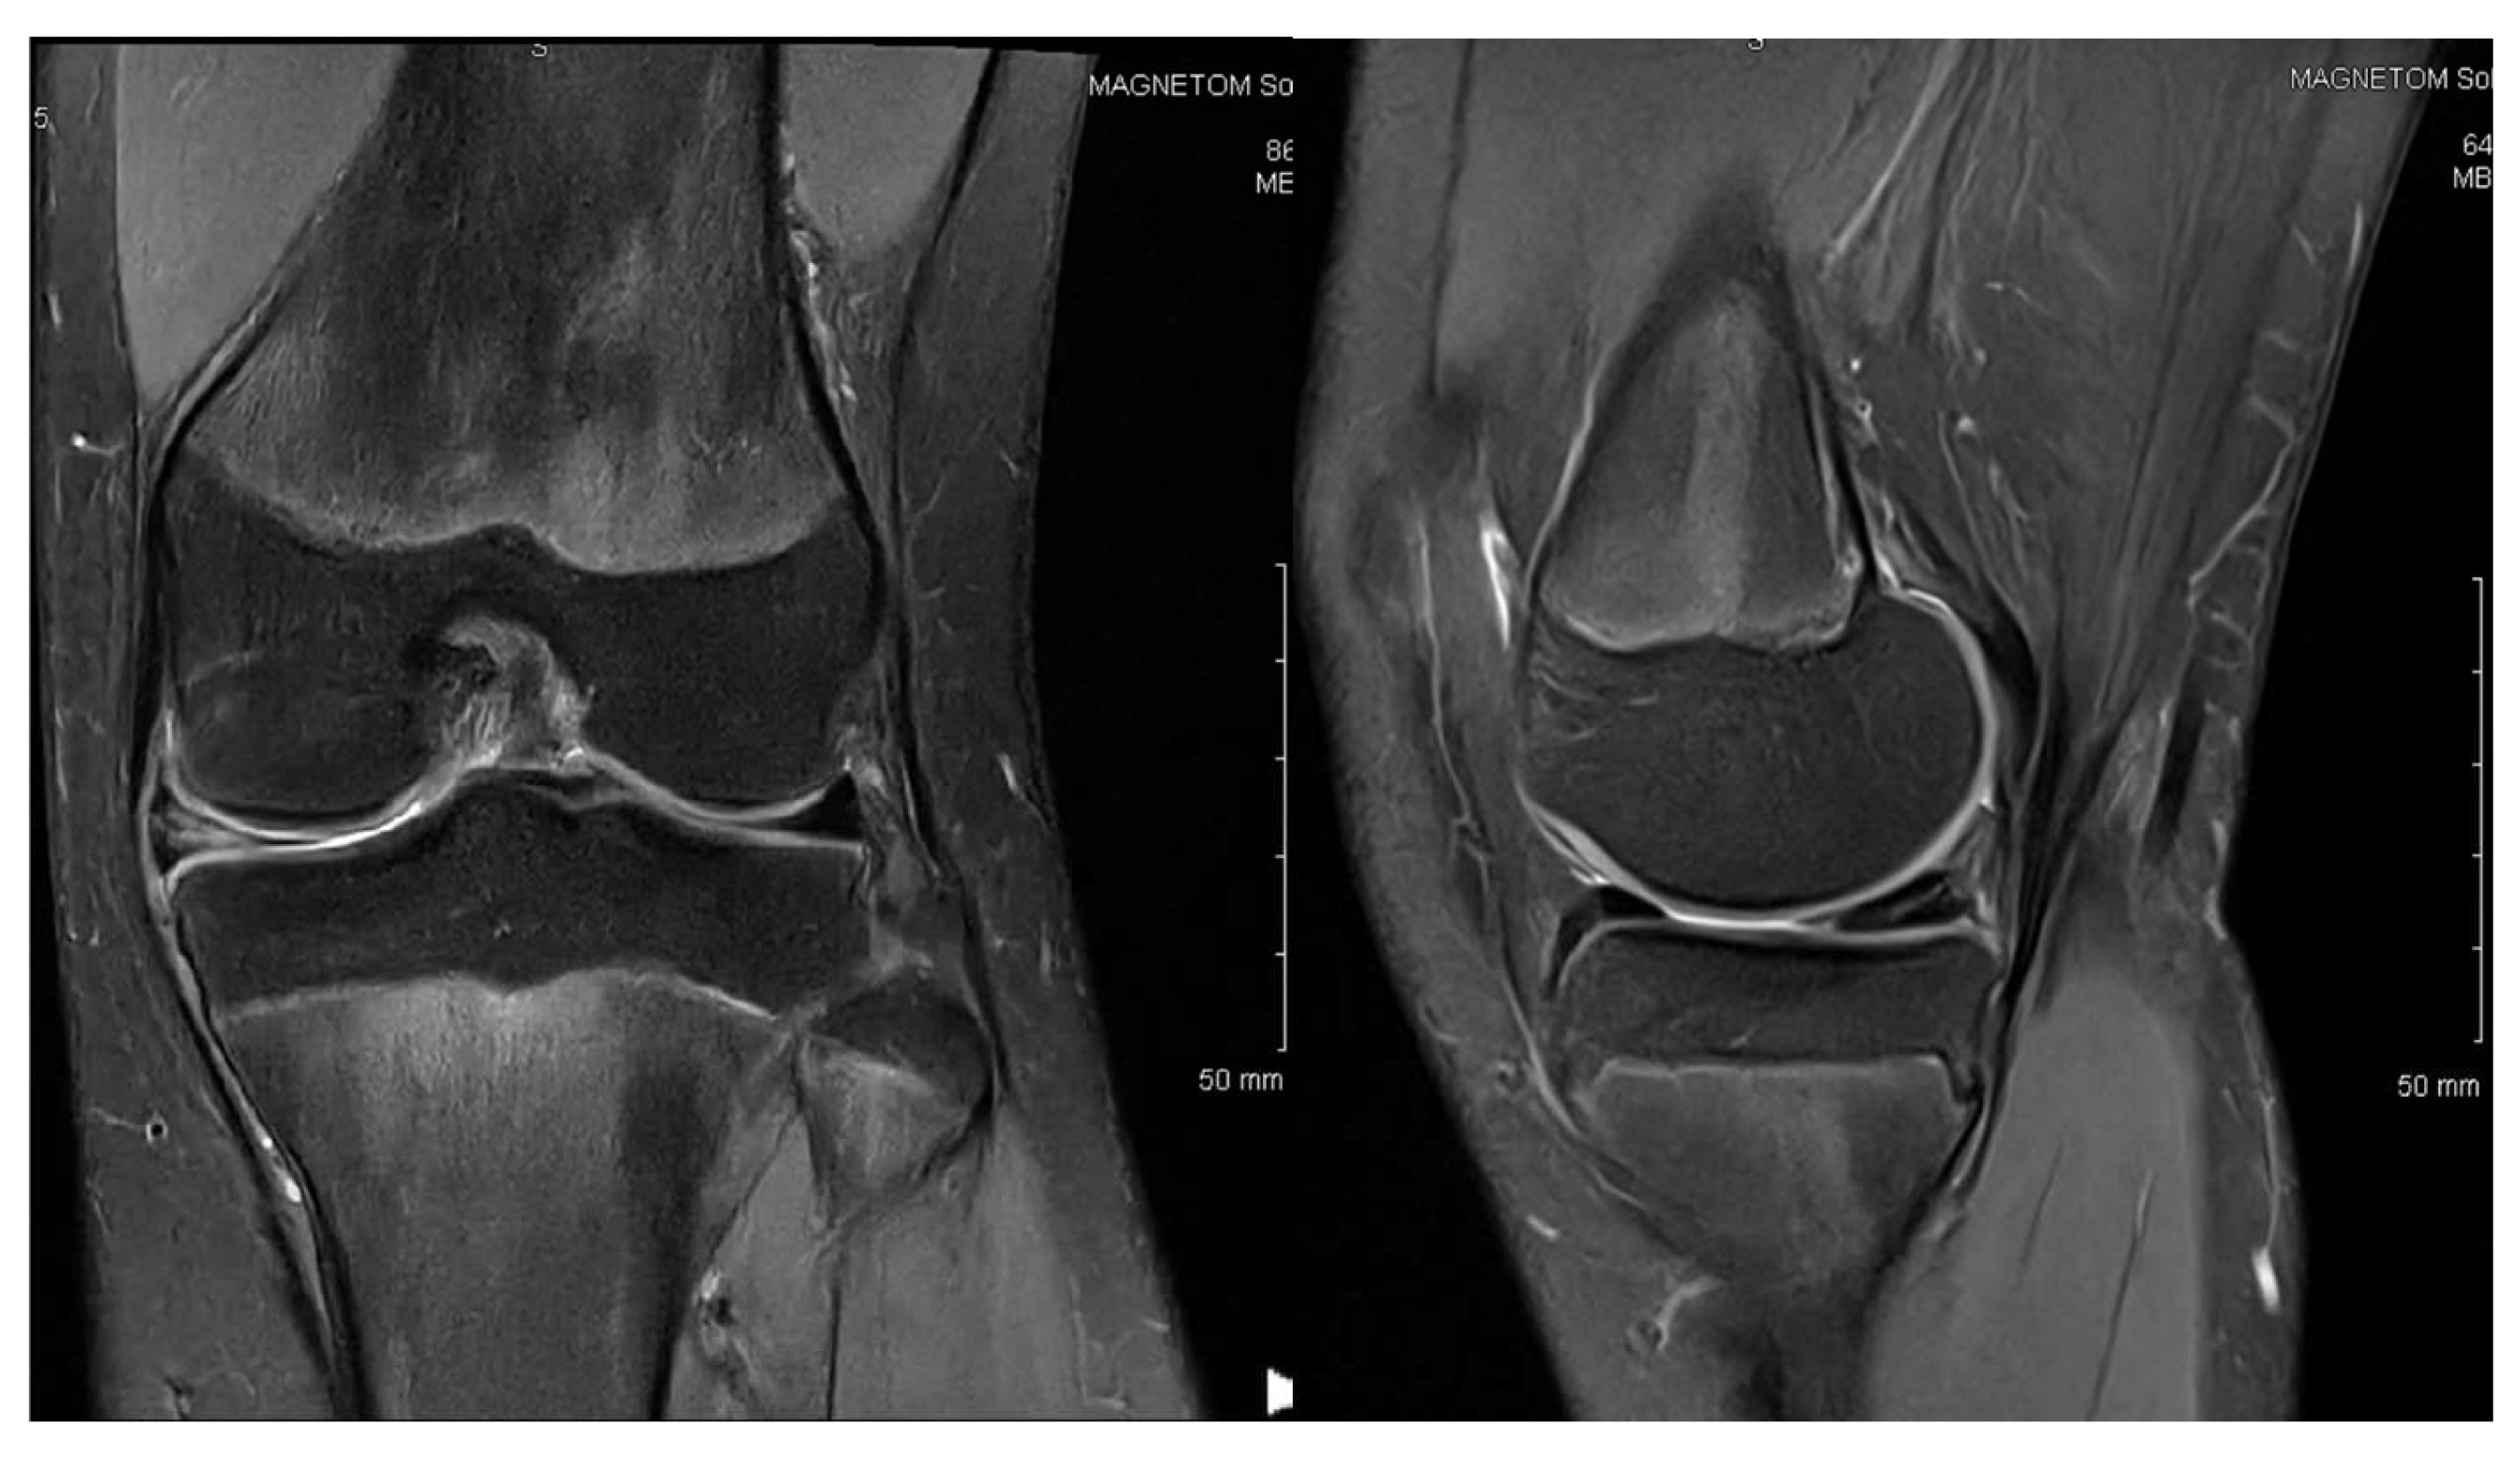

3.1. Case 1—P.E.

3.2. Case 2—S.C.S.

3.3. Case 3—G.L.

| P.E. | 12 | Bilateral (symptomatic right) | Chronic pain, effusion, normal ROM | None | 3 surgeries: partial meniscectomy (12 years), suture for horizontal tear (13 years), suture for radial tear (14 years) | 1 year after third surgery: symptom-free, resumed school sports |

| S.C.S. | 13 | Left | Pain, occasional locking, normal ROM | Dancing | 1 surgery: partial meniscectomy and suture for horizontal tear (13) | 6 months: symptom-free, full ROM, resumed dancing |

| G.L. | 14 | Bilateral (symptomatic right) | Pain, medial tenderness, normal ROM | Basketball | 1 surgery: partial meniscectomy and suture for horizontal tear (14) | 6 months: symptom-free, full ROM |